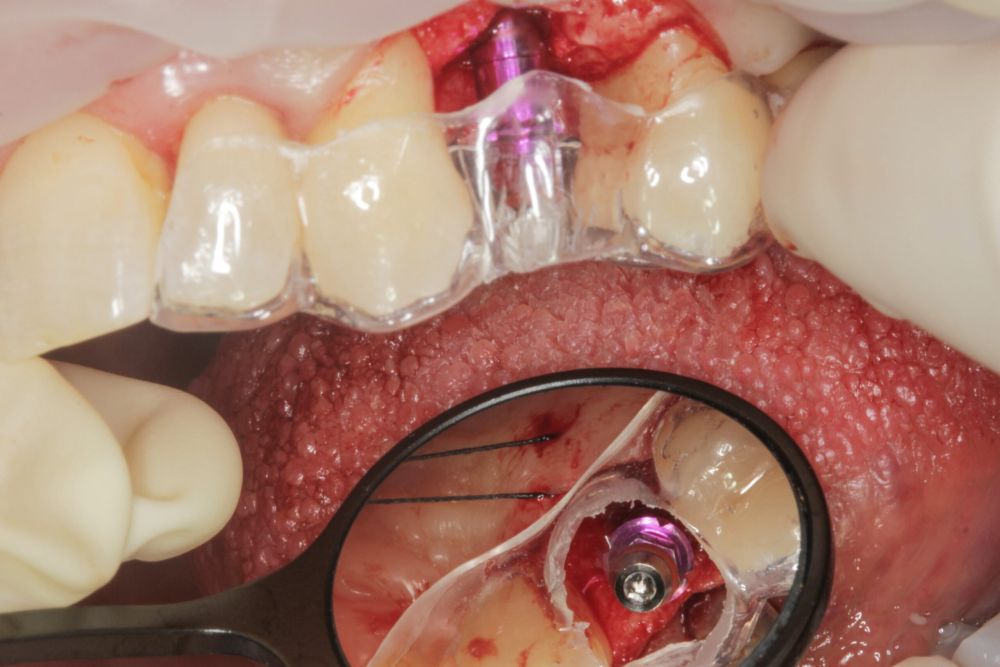

Todas las cirugías fueron realizadas por un único cirujano bajo anestesia local, tras un diagnóstico previo del lecho óseo mediante tomografía volumétrica (CBCT) procesada con un software específico de planificación implantológica (BTI-Scan III). La preparación del lecho implantario se llevó a cabo siguiendo la técnica de fresado biológico a bajas revoluciones descrita por Anitua y cols.19.

En cuanto a la rehabilitación protésica, en todos los casos se utilizó una prótesis atornillada con transepitelial para prótesis unitaria. La supervivencia de las prótesis fue del 100%, sin encontrarse fracaso en ninguna de ellas al igual que los implantes, con un tiempo de seguimiento de tres años. Durante el primer año, en las visitas de control, ninguno de los implantes mostró sangrado al sondaje ni inflamación de los tejidos periimplantarios. La media de la pérdida ósea en este punto fue de 0,32 mm (+/- 0,60) y la media de la pérdida ósea distal de 0,31 (+/- 0,48). A los dos años, no se registraron tampoco signos inflamatorios en ninguno de los implantes y la pérdida ósea mesial del conjunto fue de media de 0,38 mm (+- 0,54) y la distal de 0,64 mm (+/- 0,70). En la última visita a los 3 años, los tejidos periimplantarios siguieron estables, sin signos de inflamación y la media de la pérdida ósea mesial fue de 0,40 mm (+/- 0,53) y la distal de 0,69 (+/- 0,55) (Figura 5). En las Figuras 6-12 se muestra uno de los casos incluidos en el estudio.

Estos datos de supervivencia y pérdida ósea podrían relacionarse con la estricta estandarización del protocolo quirúrgico, la utilización de fresado biológico a bajas revoluciones y el uso sistemático de prótesis atornilladas con transepitelial, lo que reduce el riesgo de microfiltración y facilita la estabilidad de los tejidos blandos21-24. La principal limitación de este estudio es el reducido tamaño muestral, lo que impide extraer conclusiones definitivas. Sin embargo, se trata de una de las pocas series que analiza específicamente el comportamiento de implantes extracortos y estrechos en rehabilitaciones unitarias, lo que aporta un valor clínico añadido frente a la mayoría de publicaciones centradas en prótesis parciales o completas.